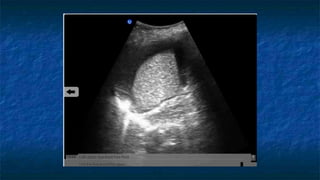

Extended FAST (E-FAST)

RUQ, LUQ views:

 Check above diaphragm for hemothorax

 CXR = US in detection of hemothorax

Ma and Mateer. Ann Emerg Med, 1997

 50-175cc vs. 20cc or less

 US does not replace CXR

Hemothorax

KD

SP

FF

D

Pleural Fluid

Extended FAST (E-FAST) RUQ,LUQ views:  Check above diaphragm for hemothorax  CXR = US in detection of hemothorax Ma and Mateer. Ann Emerg Med, 1997  50-175cc vs. 20cc or less  US does not replace CXR Suprapubic view:  Check uterus for pregnancy